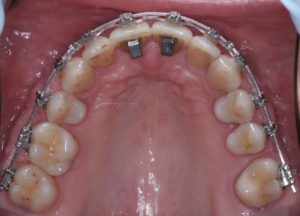

Для предварительной подготовки были привлечены пародонтолог и ортопед, поскольку отсутствие нескольких зубов, заболевание пародонта и дефекты твердых тканей зубов сопутствовали основной патологии. Проведены пародонтологические процедуры, вылечен кариес и его осложнения, изготовлены временные коронки для зубов с большим разрушением. На фото — временные коронки на боковых зубах.